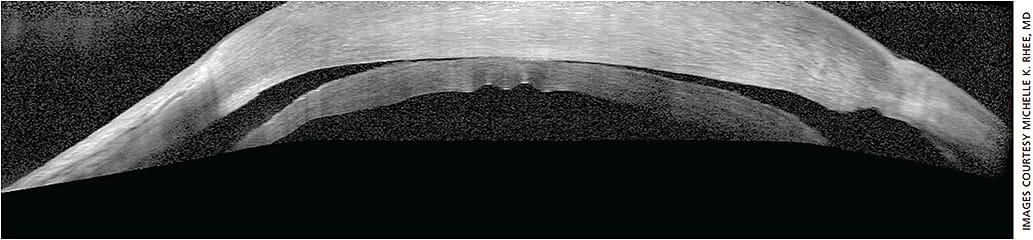

In preparation for the possibility of DSEK, consider a target postoperative refraction at about -0.75 D to -1.00 D since DSEK tends to produce a hyperopic shift in the +1.25-D range. DMEK (typically 15 μm thick and planar in configuration) also has a hyperopic shift, but less so than DSEK since there is no posterior stroma transplanted.